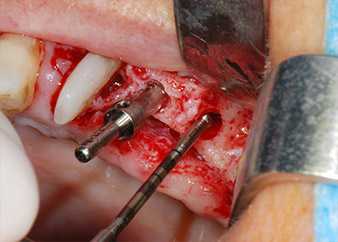

A continuación, los implantes (Restore, Keystone Dental, 3,75 mm de diámetro, 8,0 mm de longitud) se colocaron con el motor de implantes (figuras 11 y 12).

Las deficiencias óseas alrededor de los implantes, en el área mesial de la pieza 27 y alrededor de la raíz bucal de la pieza 24, se obturaron con partículas sustitutas de hueso xenógeno (Geistlich Bio-Oss) y se cubrieron con una membrana de colágeno absorbible (Geistlich Bio-Gide) a efectos de realizar un aumento mediante GBR

(figuras 13 y 14).